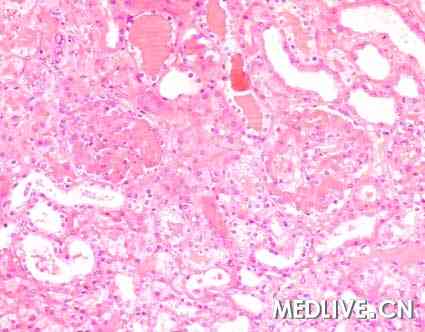

肾活检图片如图。

图1 HE染色,200×

临床诊断:血栓性微血管病(起源于供体)

血栓性微血管病(Thrombotic microangiopathy, TMA)定义为毛细血管和(或)小动脉内血栓形成。TMA是公认的严重肾移植术后并发症之一。该病血管内溶血的临床特点并不总表现出来。该病分为新发TMA和复发TMA,多数新发TMA与环孢菌素治疗有关。病毒感染、严重肾缺血和急性血管性排斥反应是较少见原因。

肾小球毛细血管或小动脉内纤维性血栓形成可用于诊断血栓性微血管病。全身性TMA诊断依据是出现血小板减少和微血管病性溶血的证据。本例中活检结果与血栓性微血管病特征一致,但是无任何全身性溶血改变者考虑有局部TMA。